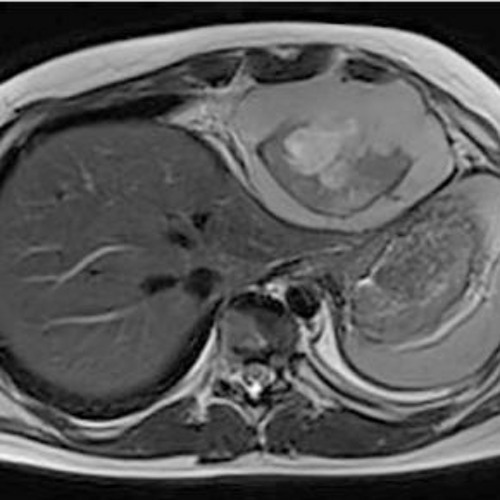

Case Report: Intrathoracic Synovial Sarcoma with BRAF V600E Mutation

A new case report was published in Oncotarget's Volume 14 on July 7, 2023, entitled, “Intrathoracic synovial sarcoma with BRAF V600E mutation.”